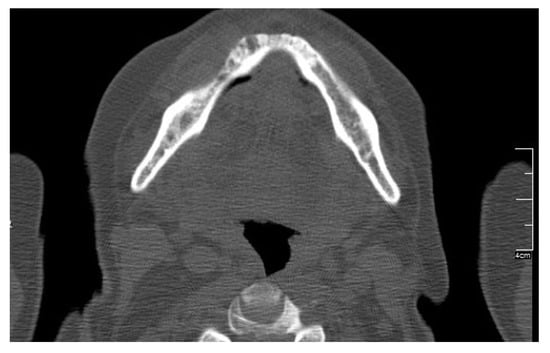

| Location | ||||||||

| Upper jaw | x | x | 2 | 6 | ||||

| Lower jaw | x | x | x | x | 4 | 8 | ||

| Both jaws | 2 | |||||||

| Stage | ||||||||

| Ia | x | 1 | 1 | |||||

| Ib | x | x | 2 | 3 | ||||

| IIa | x | 1 | 2 | |||||

| IIb | x | 1 | 5 | |||||

| IIIa | ||||||||

| IIIb | x | 1 | 5 | |||||